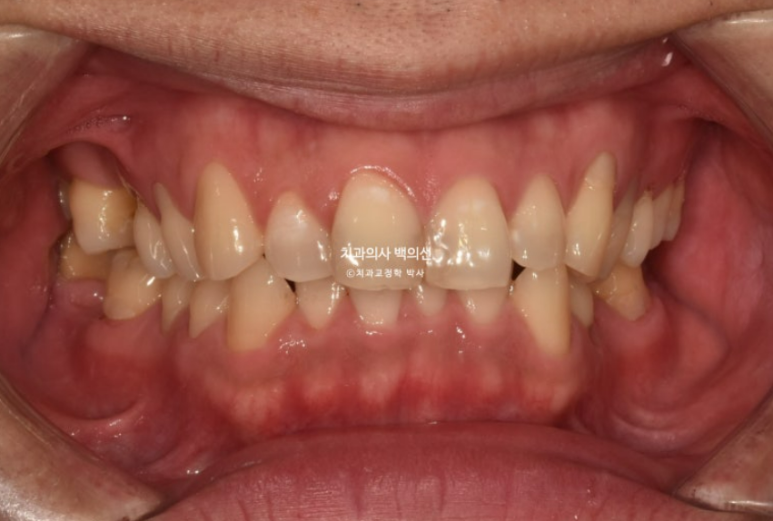

중심선 불일치와 심한 과개교합, 송곳니 덧니 등이 보입니다.

24.05